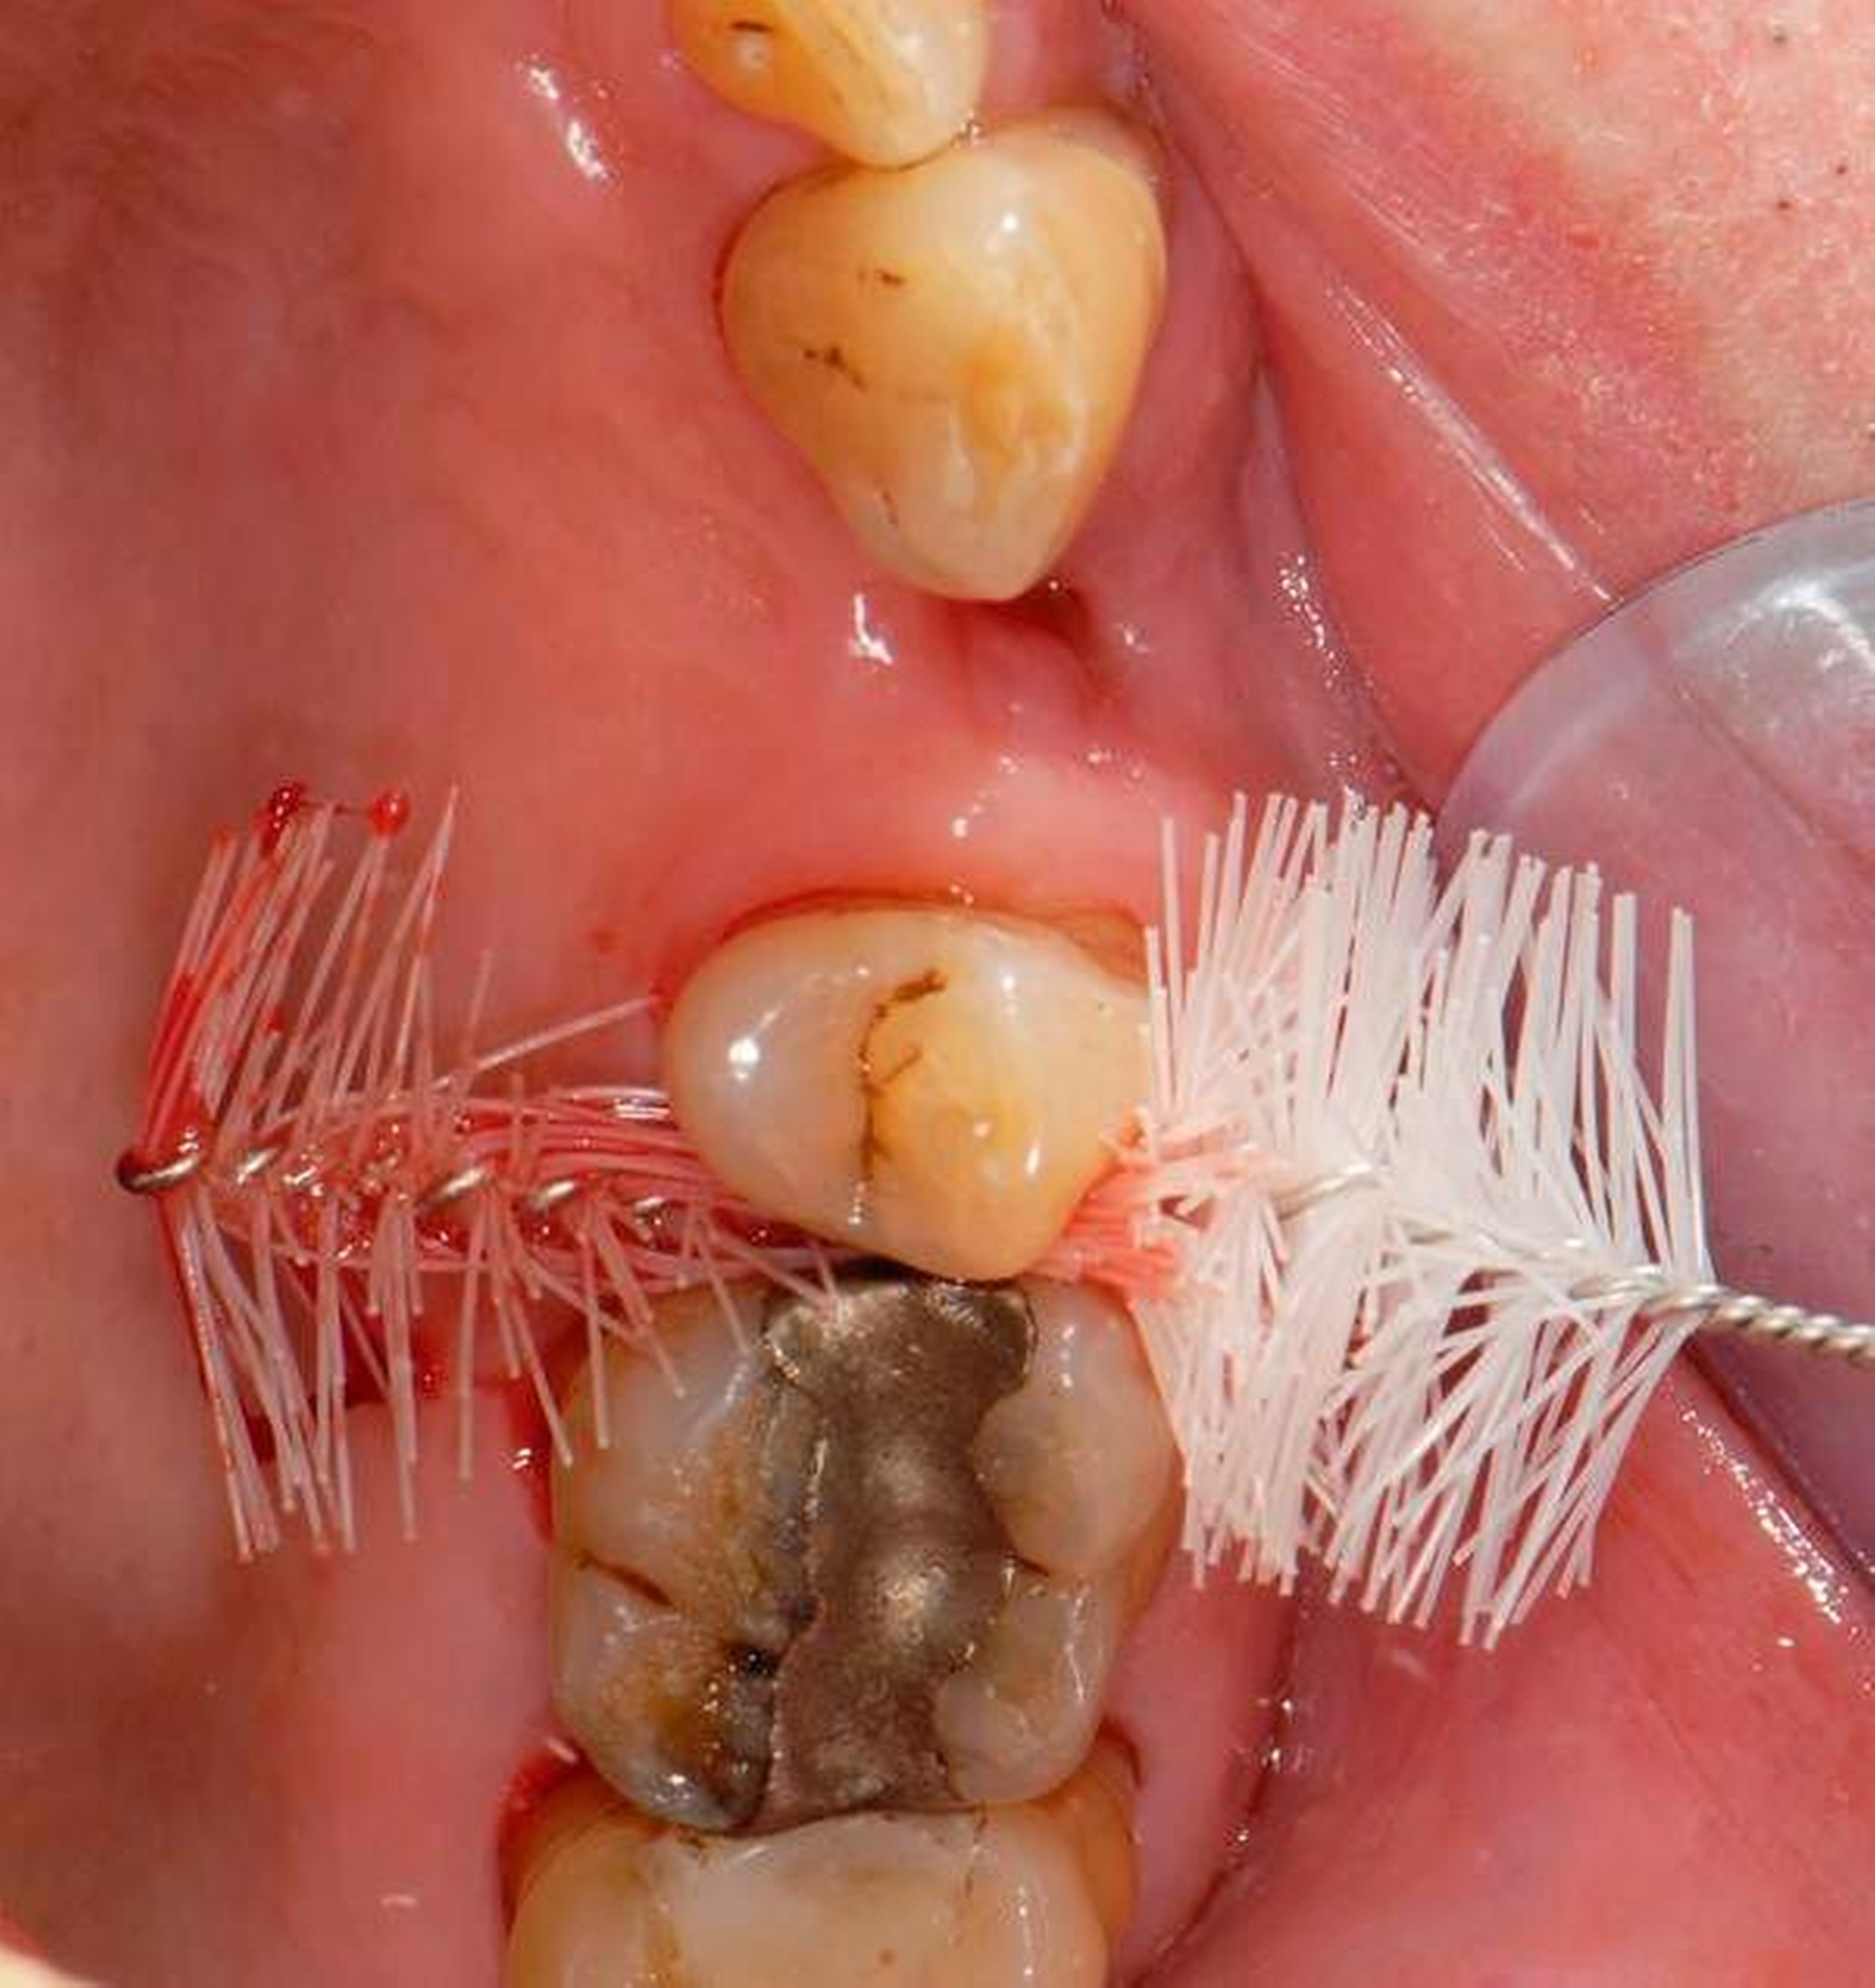

Abbildung 2: Direkte Teilüberkronung im Seitenzahnbereich (R1-Technik)

In den Abbildungen 1 bis 3 werden Optionen für frugale Interventionen auf restaurativem Sektor aufgeführt. Es handelt sich um direkte Vollüberkronungen im Frontzahnbereich (hier: hergestellt in R1-Technik / einphasig) (Abbildung 1), direkte Teilüberkronungen im Seitenzahnbereich (hier: hergestellt in R1-Technik / einphasig) (Abbildung 2), Reparatur-Restaurationen im Seitenzahnbereich (hier: hergestellt in R2-Technik / zweiphasig) (Abbildung 3). Technische Einzelheiten zur Vorgehensweise und den Ergebnissen sind an anderer Stelle beschrieben (Literatur siehe oben).

Für die in Abbildung 2 dargestellte Situation eines tief zerstörten Prämolaren gelten ähnliche Charakteristika. Es gibt in der restaurativen Zahnheilkunde viele Neuerungen, die das Behandlungsspektrum vergrößert haben. Dazu zählen unter anderem: